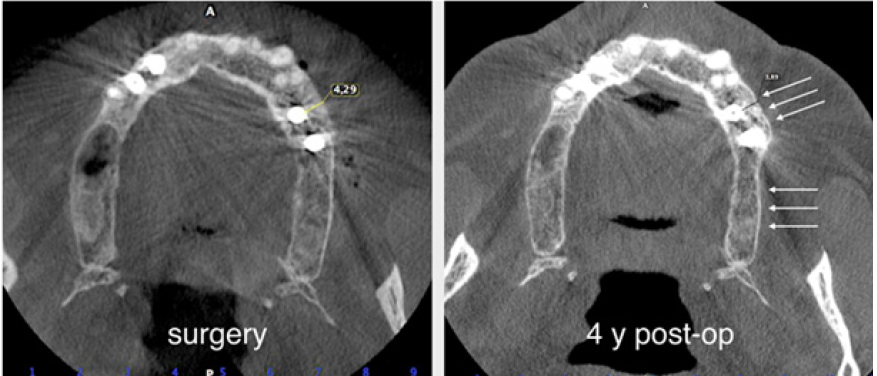

A male patient 40 years old, affected by periodontitis grade IV referred to the clinic looking for a solution for his edentulous ridges. The CBCT showed a severely resorbed ridge at some points only one mm thick. Patient was in good health and accepted to undertake GBR in all edentulous areas by mean of the F.I.R.S.T. technique. The indication in this specific case was justified by the severe horizontal resorption, using some kind of ‘sticky bone’ would enhance the chances to obtain stability of the graft and good support for the cortical lamina placed on top of the augmented area. After local anesthesia with Articaine 1.200.000 full thickness buccal and lingual flaps were elevated to display what was already known from the CBCT (Figure 16). With a piezo surgical device, the buccal cortical bone was perforated in several different points to

The protocol used to hydrate the cortico cancellous porcine xenograft (GenOs Osteobiol, Tecnoss, Coazze, Italy) was the same previously described, the use of the FS eases the stability and stickiness of the graft that adheres well to the edentulous ridge now measuring 5mm in width. The addition of the cortical lamina glued by means of FS to a well set bone graft further increases the size of the ridge (Figure 18). In this specific case was important to over-contour the regeneration anticipating some kind of remodeling due to the fact that the patient was using a removable partial denture. Because of his edentulism it was not possible to restrain the patient from the use of his denture, for this reason the augmentation provided an overcorrection of the defect anticipating some kind of remodeling with the use of the denture (Figure 19). Six months later it was possible to insert 3.4mm diameter implants in the ridge that at baseline was 1 mm thick, the new ridge was now 5mm wide. The two implants were restored with a long term temporary restoration (acrylic re-inforced with Kevlar) and three years after loading everything remained stable (Figure 20-23).

The protocol used to hydrate the cortico cancellous porcine xenograft (GenOs Osteobiol, Tecnoss, Coazze, Italy) was the same previously described, the use of the FS eases the stability and stickiness of the graft that adheres well to the edentulous ridge now measuring 5mm in width. The addition of the cortical lamina glued by means of FS to a well set bone graft further increases the size of the ridge (Figure 18). In this specific case was important to overcontour the regeneration anticipating some kind of remodeling due to the fact that the patient was using a removable partial denture. Because of his edentulism it was not possible to restrain the patient from the use of his denture, for this reason the augmentation provided an overcorrection of the defect anticipating some kind of remodeling with the use of the denture (Figure 19). Six months later it was possible to insert 3.4mm diameter implants in the ridge that at baseline was 1 mm thick, the new ridge was now 5mm wide. The two implants were restored with a long term temporary restoration (acrylic re-inforced with Kevlar) and three years after loading everything remained stable (Figure 20-23).

Figure 19: A comparison of the ridge before and after augmentation.

Figure 20: A comparison between the original ridge and the new volume after six months.